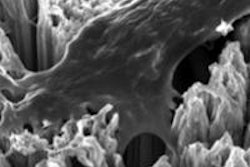

In the course of the same study, researchers performed a 2-week bone-healing study where they compared newly prepared acid-etched implants versus 4-week-old similarly prepared implants in a rat femur model. After 2 weeks, contiguous, extensive bone formation covered a large area of the new implants. There was little soft-tissue intervention in the new formed bone and titanium. In the old implants, the coverage was limited, fragmented, and localized. There was much more soft-tissue intervention as well.

"The BIC for the new surface reached more than 90% whereas it was lower than 60% for 4-week-old implants," the researchers noted. Additionally, there was greater BIC at 2 weeks of healing in the new implants than after 4 weeks of healing in the older implants.